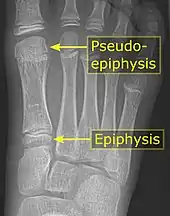

Pseudo-epiphysis

A pseudo-epiphysis is an epiphysis-looking end of a bone where an epiphysis is not normally located.[4] A pseudo-epiphysis is delineated by a transverse notch, looking similar to a growth plate.[4] However, these transverse notches lack the typical cell columns found in normal growth plates, and do not contribute significantly to longitudinal bone growth.[5] Pseudo-epiphyses are found at the distal end of the first metacarpal bone in 80% of the normal population, and at the proximal end of the second metacarpal in 60%.[4]